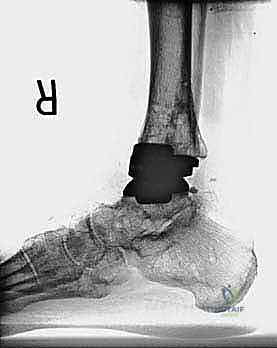

مراجعة مفصل الكاحل الصناعي هي إجراء جراحي ضروري لمعالجة المشاكل التي قد تنشأ بعد الجراحة الأولية، مثل كسور الكعبين أو عدم استقرار المفصل. يتضمن العلاج التشخيص الدقيق عبر الأشعة السينية والتصوير المقطعي، يليه التدخل الجراحي لتثبيت الكسور واستعادة وظيفة الكاحل، مع التركيز على التعافي المبكر.

تُعد جراحة مراجعة مفصل الكاحل الصناعي (Revision Total Ankle Replacement) من الإجراءات الجراحية المتقدمة والبالغة الدقة في عالم جراحة العظام الحديثة. لا تقتصر هذه الجراحة على مجرد استبدال مفصل تالف بآخر جديد، بل هي عملية إنقاذ معقدة للغاية تهدف إلى معالجة المشاكل الميكانيكية والبيولوجية التي تنشأ بعد الجراحة الأولية. من أبرز هذه المشاكل: الفشل الميكانيكي للمفصل، تحلل العظام (Osteolysis)، أو حدوث كسور معقدة في الكعبين (Malleolar Fractures) المحيطة بالمفصل الصناعي. يتطلب هذا الإجراء تقييماً سريرياً وشعاعياً دقيقاً يشمل التصوير المقطعي ثلاثي الأبعاد والأشعة السينية، يليه تدخل جراحي دقيق لاستعادة التوازن الحيوي والميكانيكي للكاحل والحفاظ على الطرف من البتر أو الدمج.

- الأشعة السينية مع تحميل الوزن (Weight-bearing X-rays): لتقييم الزوايا الميكانيكية وتحديد مدى هبوط المفصل أو وجود كسور في الكعب.

كسور الكعبين (Malleolar Fractures) المصاحبة للمفصل الصناعي

من أعقد التحديات التي تواجه جراحي العظام هي حدوث كسور في الكعب الداخلي (Medial Malleolus) أو الخارجي (Lateral Malleolus) في وجود مفصل صناعي. تحدث هذه الكسور لعدة أسباب:

1. ترقق العظام: حول المفصل الصناعي نتيجة لعدم استخدام الطرف بشكل طبيعي (Stress Shielding).

2. الاصطدام الميكانيكي (Impingement): إذا كان حجم المفصل الصناعي أكبر من اللازم، فقد يضغط على الكعبين من الداخل ويؤدي لكسرهما بمرور الوقت.

3. الإصابات المباشرة: مثل السقوط أو التواء الكاحل.

علاج هذه الكسور يتطلب مهارة فائقة من الدكتور محمد هطيف، حيث يتم استخدام تقنيات الجراحة الميكروسكوبية وتثبيت الكسور باستخدام صفائح معدنية دقيقة ومسامير (Locking Plates) دون المساس بثبات المفصل الصناعي، أو يتم دمج علاج الكسر ضمن عملية مراجعة المفصل الكلية إذا كان المفصل نفسه تالفاً.

يتم إدخال المفصل الجديد المخصص للمراجعة، والذي يحتوي غالباً على سيقان (Stems) تدخل عميقاً في عظمة الساق وعظمة الكاحل لضمان الثبات الميكانيكي. في حال وجود كسور في الكعب، يتم تثبيتها في هذه المرحلة.